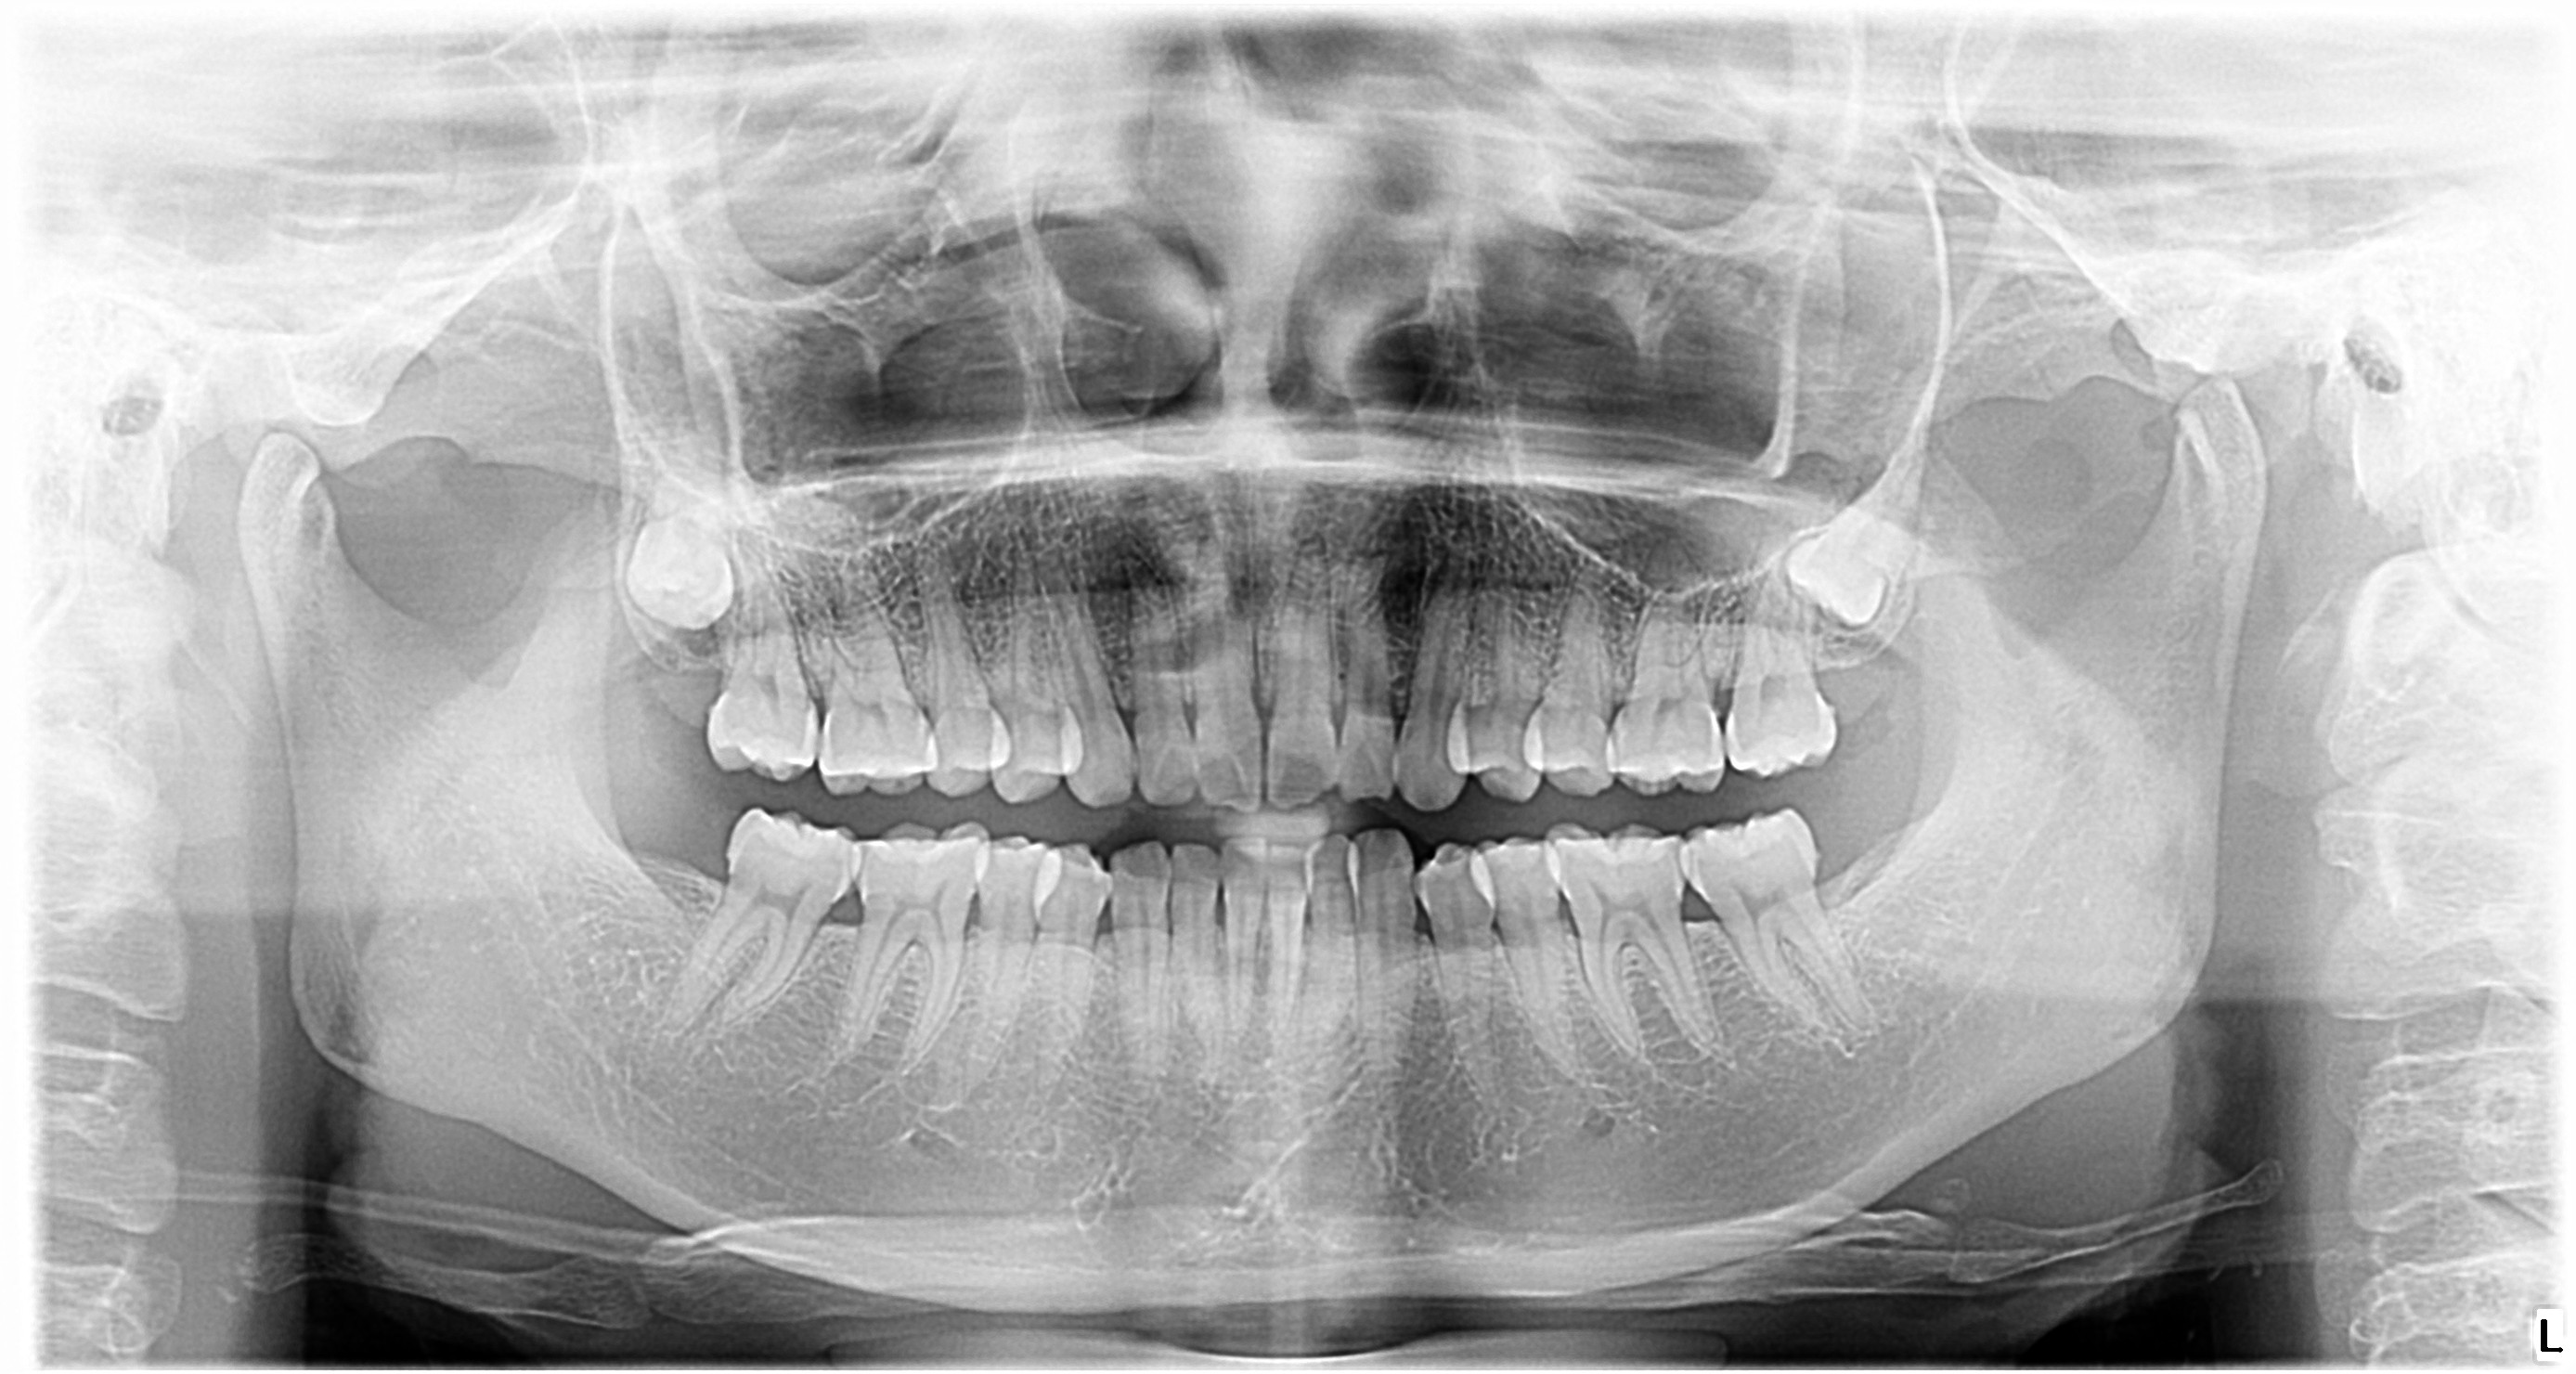

牙齿的形态图与口腔颌面解剖图_恒牙

一,口腔颌面部界限与分区

首页 嘉友资讯中心 合学关节 牙医基础知识:口腔颌面